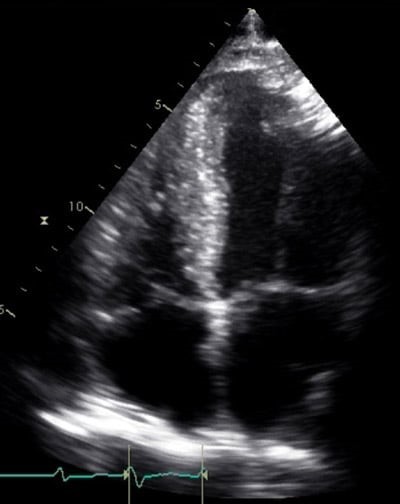

A) A 77-year-old man, a doctor by profession presented with a history of acute shortness of breath with sweating and anxiety. His EKG revealed STEMI with STE in V1-V6, I,avL suggestive of extensive anterior wall MI. His echocardiogram revealed severe LV dysfunction with EF of 28% and RWMA with severe hypokinesia of mid and apical IVS and lateral wall, anterior wall with akinetic apex.

However, speckle tracking imaging revealed an evil eye pattern on a bull plot which led to suspicion of Takotsubo CMP.